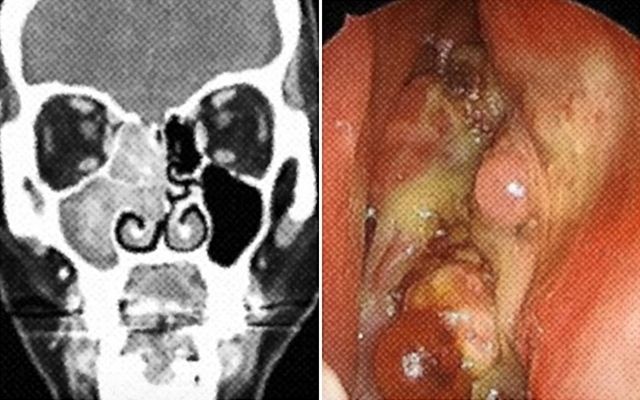

서울대병원에 따르면 부비동암은 코안의 빈 곳인 '비강' 주위의 동굴 같은 부비동에 발생하는 희소암이다. 비강과 부비동에 발생하는 악성종양은 인체의 악성종양 가운데 1% 이하이며, 두경부 악성종양의 3~5%를 차지한다. 보건복지부와 국립암센터가 발표한 2021년 국가암등록통계에 따르면 부비동암은 연간 인구 10만 명당 약 0.2~0.5명에 발생하며, 남성이 여성보다 2~3배 높은 발병률을 보인다.

부비동암은 초기에 증상이 없거나 단순 코막힘, 콧물, 후각 감퇴 등 비염과 유사한 증상이 나타나 조기에 발견하기 어렵다. 암이 발생한 부위에만 머물러 있는 초기 단계에서 발견되면 치료 성과가 좋지만, 암을 발견했을 때는 이미 병이 상당히 진행됐을 가능성이 크다. 조기 발견도 어려운데 병의 진행이 빠른 것으로 나타났다. 주변에 뇌와 눈 같은 중요 신체 부위와 인접해 있지만, 아직 치료법이 확립되지 않은 상태다. 1960년대까지는 치료 성공률이 28% 수준이었으나 진단기법 발전과 적극적인 수술 및 치료로 1990년대에는 전반적인 생존율이 51%까지 높아졌다. 5년 생존율은 59.5%로 보고됐다.

따라서 반복적이고 지속적인 코막힘, 콧물, 코피 등의 증상이 있을 경우나 비염·축농증 증상이 수개월 이상 지속되는 경우 등엔 코 내시경 검사를 통해 조기에 발견하는 것이 치료 효과를 높이는 유일한 방법이다. 아울러 흡연과의 관련성이 보고되고 있어 금연도 부비동암 예방엔 필수적이다.